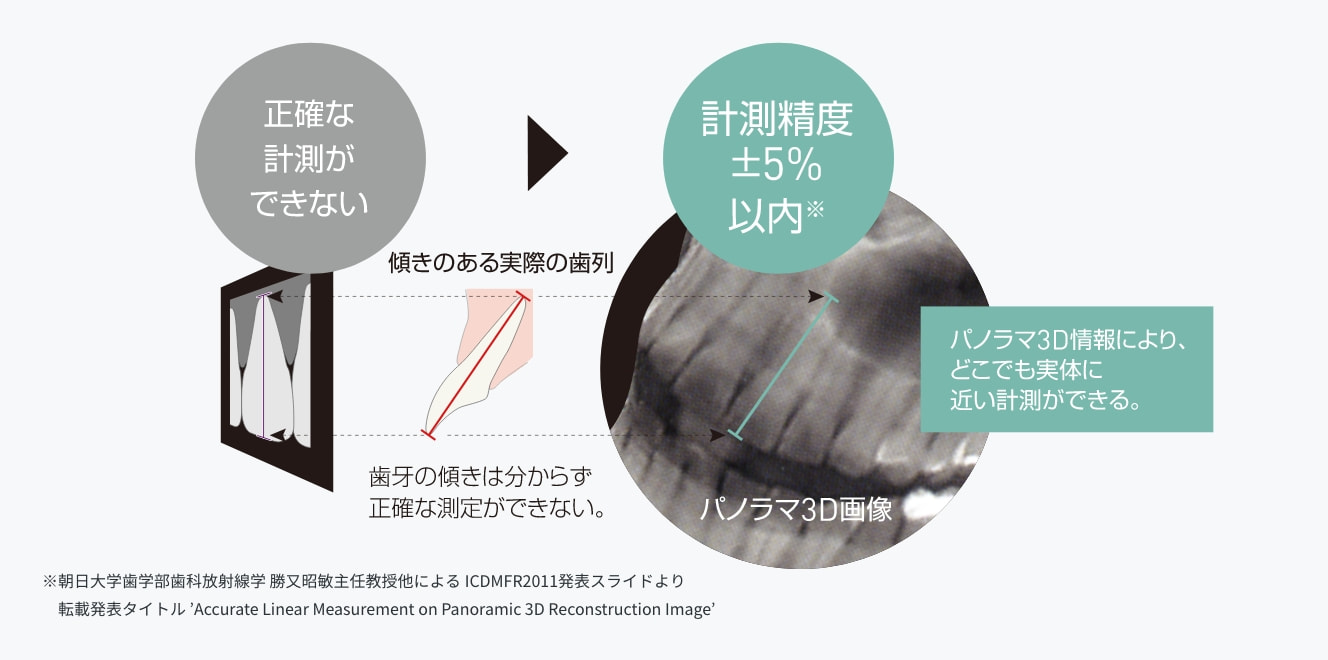

高精度距離計測

3D空間上の座標情報に基づき構築された3Dモデルから、平面上で指定された2点間を立体的に計測。

精度の高い距離計測が可能になりました。

パノラマ画像で距離計測が正確でない理由

2D上の距離計測は、歯牙の傾きを考慮した正確な距離計測が不可能でした。

パノラマ3D情報による計測

3Dオートフォーカス技術によるパノラマ3D情報があるため、精度の高い距離計測が可能です。